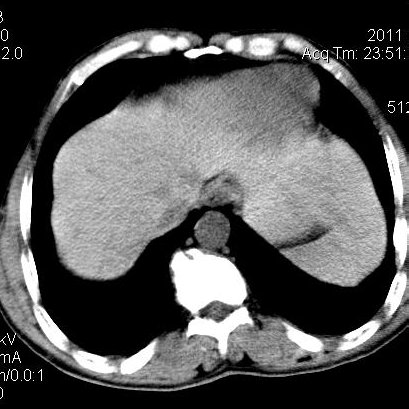

肝左叶发育异常

男性,55岁,骑摩托车摔倒后入院,自述右上腹疼痛

[backcolor=#FF0000]第一次诊断的时候也是这么肯定,可是床旁超声检查并没有发现明显异常,而且患者的一般症状都良好。还好临床只是保守治疗,没有立即手术,第二次复查的时候没有一点变化,又做了MRI检查,没有血肿,

这是一例肝左叶发育异常的,很个性吧~[/backcolor]